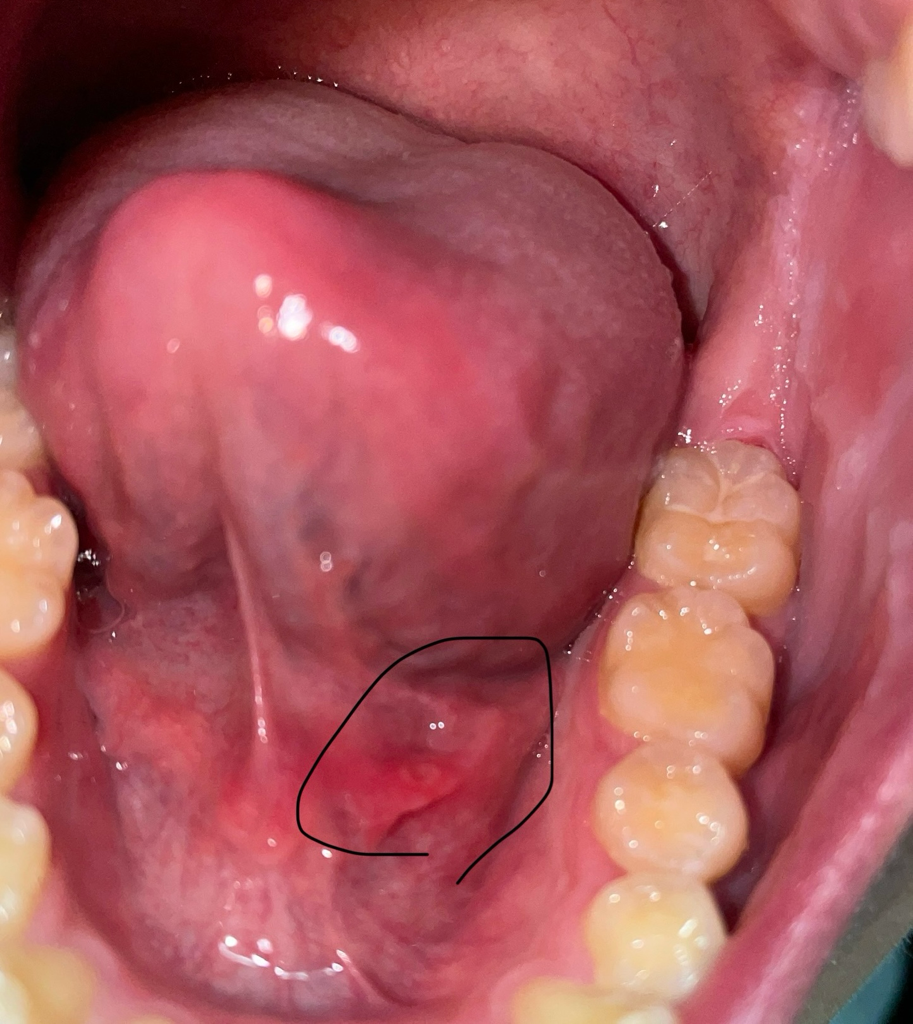

입안 혀 아래 쪽에 뭔가 났어요 뭔가여?

입아래 혀 아래쪽에 무언가 났어요 이물감 들고 건드리면 따거워요 이거 어캐하면 나아요?? 생긴지는 3-4일됬어요. 어떻게해야 없앨까요..